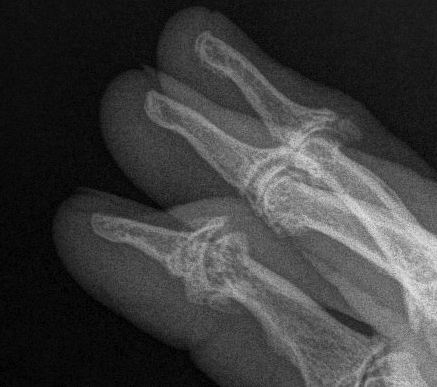

Psoriasis

Hand X-ray

Periarticular phalangeal erosions

- asymmetrical

- no periarticular osteopenia

Periosteal new bone formation along MC / MT shafts

DIPJ

- typical 'Pencil in cup' deformity of DIPJ

- P3 tuft resorption & whittling